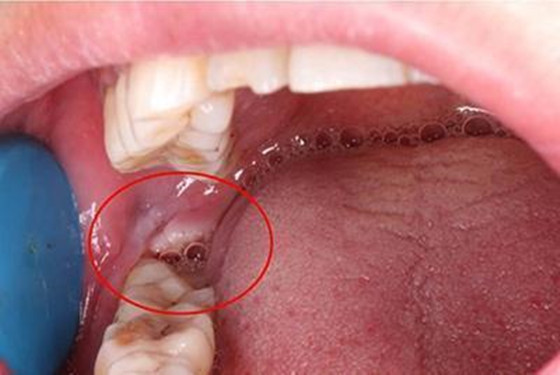

2016年12月22日,我做了一个今生都后悔的决定,拔下牙智齿,然而感染了,已确诊是干槽症,距离今天已经8天了,每天都生不如死!生无可恋!

话又说回来并不是每个人拔智齿后都会得干槽症,机率很小的,一般创口比较大,比较难拔,阻生横长的厉害的比较容易得干槽症,还有就是我这种有洁癖拔牙后老觉得嘴巴有血腥味然后老是漱口的人,把血凝块漱没了直接感染了的,所以拔牙后千万要注意不能乱刷牙漱口的。